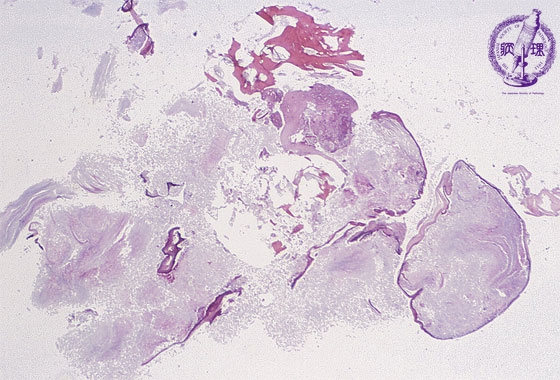

Microscopic findings: Fragments are taken from the middle ear. Keratinaceous materials, bone fragments and granulation tissues are seen.